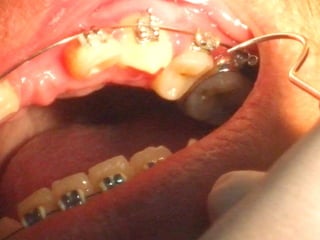

• Paciente de 25 años con

Plastia de maxilares para implantes dentales.

La conformación quirúrgica de un contorno alveolar adecuado es

determinante para la correcta aplicación y aceptación de los implantes

de titanio, aquí proponemos una técinica para lograr el espesor óseo

suficiente y la corrección estética del proceso, ya que antiguamente al

extraer un diente se acostumbraba presionar las tablas alveolares

“para cohibir la hemorragia”, con el colapso subsiguiente de la región.

Incisión

Disección cuidadosa del colgajo

Defecto óseo a corregir